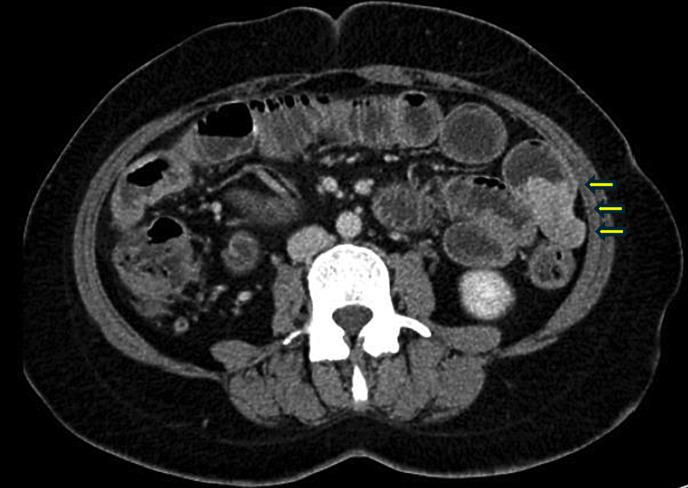

Case presentation: We report a case of a 45-year-old Singaporean woman with café-au-lait macules and cutaneous neurofibromas who presented with occult obscure gastrointestinal bleeding and was eventually discovered to have a bleeding jejunal GIST. This finding, considered together with her cutaneous signs, eventually led to the diagnosis of NF1.